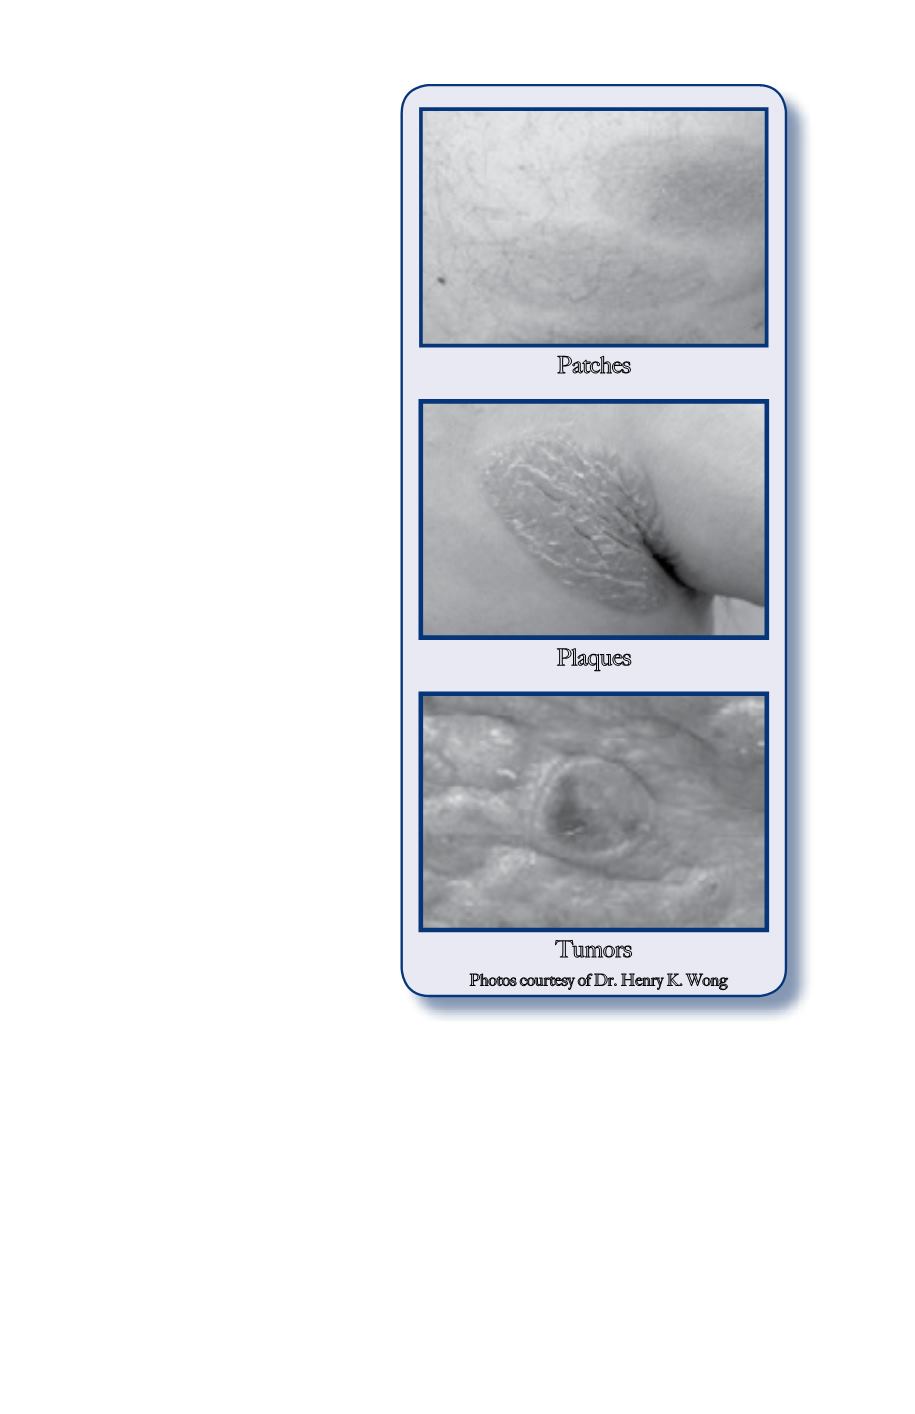

Tumors are raised “bumps”

or “nodules” which may or

may not ulcerate (open sores).

A common characteristic

is itching, although not all

patients experience this

symptom. Most of the time

patients present with patches

or plaques. Only rarely are the

tumors the presenting lesion.

Tumors

Plaques

Patches

Photos courtesy of Dr. Henry K. Wong